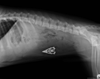

For the past 8 years, Veterinary Practice News has had an annual x-ray contest for the craziest things pet's have eaten. Here are the winners for 2013.